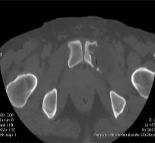

建议15-16:骨转移的治疗。DTC患者既往手术甲状腺切除术,放射性碘难治性和疼痛性骨转移已通过经动脉栓塞治疗病变,然后进行CT引导下4探针冷冻消融。